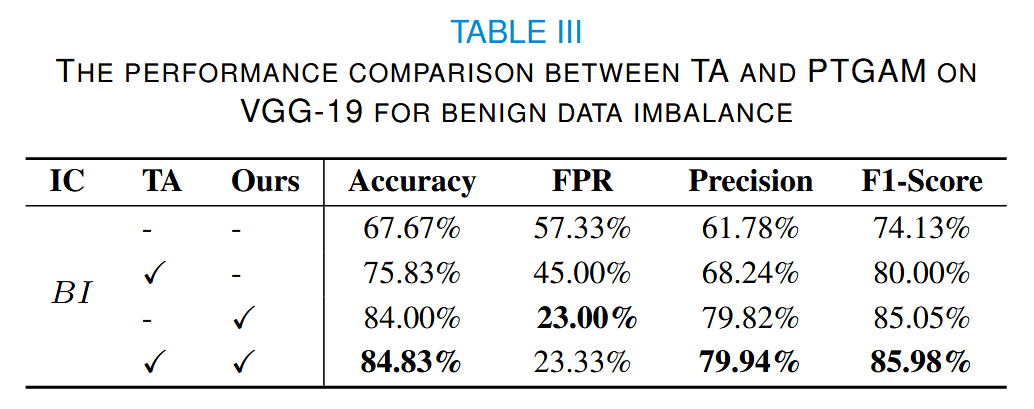

实验结果如表III所示,表中的 IC 表示不平衡类别,即数据集中稀缺的数据。

此外,我们还对恶性数据进行了数据增强实验,使其数据量与良性数据的数据增强设置大致相同。可以看出(表IV),我们的方法对每个类别具有相同的增强效果。

表IV中的 NPV 表示阴性预测值,即 TN/(TN + FN) 。

在良性数据稀缺的情况下,模型倾向于陷入偏向恶性类别的局部最优解。因此,我们选择假阳性率(FPR)和精确率来衡量不同增强方法的效果。可以看出,我们的方法能够显著减少假阳性。

当恶性数据稀缺时,我们选择假阴性率(FNR)和NPV。结果表明,当我们的方法与 TA 结合时,可以获得最高的准确率。然而,在FPR和FNR方面,我们的方法最大限度地减少了数据偏差的不良影响。